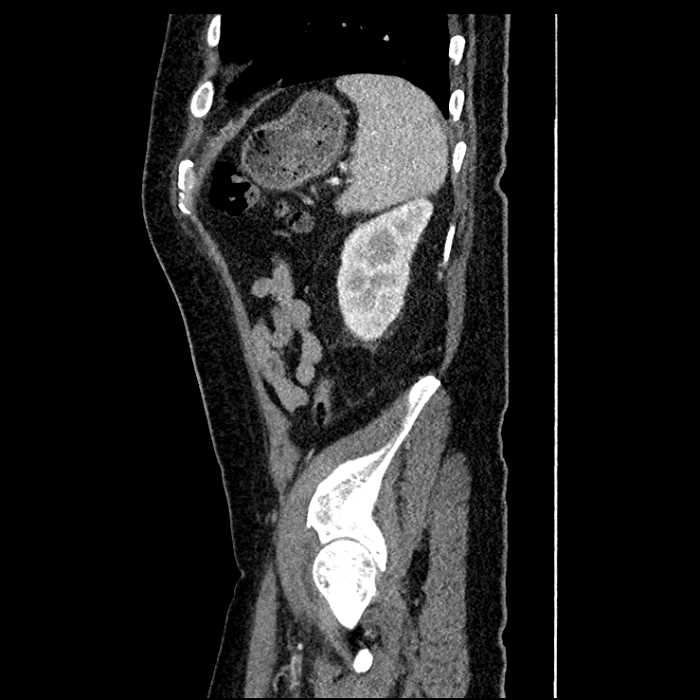

Age: 63

Sex: Male

Indication: Abdominal pain

• Large fluid density structure in hepatic segments 7 and 8 measuring 10 x 7 x 7 cm with internal septation and circumferential ill-defined low density compatible with edema

• Peripherally enhancing subcapsular collections along the anterior margin of the left hepatic lobe measuring 3 x 1 cm and 2 x 1 cm

• Clearly marginated fluid density structure in segment 7 and several other scattered tiny hypodensities, which likely represent cysts

• Mild mural thickening of a segment of the sigmoid colon with adjacent fat stranding and a 1.5 cm fluid and gas collection along the tip of an inflamed diverticulum

• Loss of the normal fat plane between this collection and adjacent loops of small bowel, which demonstrate mural thickening

• Hepatic abscess

Acute sigmoid diverticulitis complicated by a small contained perforation and a large abscess in the right hepatic lobe. Additional small subcapsular abscesses along the anterior margin of the left hepatic lobe.

Additionally, loss of the normal fat plane between the peridiverticular collection and adjacent thickened loops of small bowel raises the potential for an enterocolonic fistula.

Hepatic abscess showing the double target sign with low density internally surrounded by a thin inner enhancing rim (red arrow) and ill-defined outer low density rim (yellow arrow). Blue arrow indicates an internal septation. Red arrows: additional smaller subcapsular abscesses. Red arrow: focal contained perforation associated with diverticulitis.